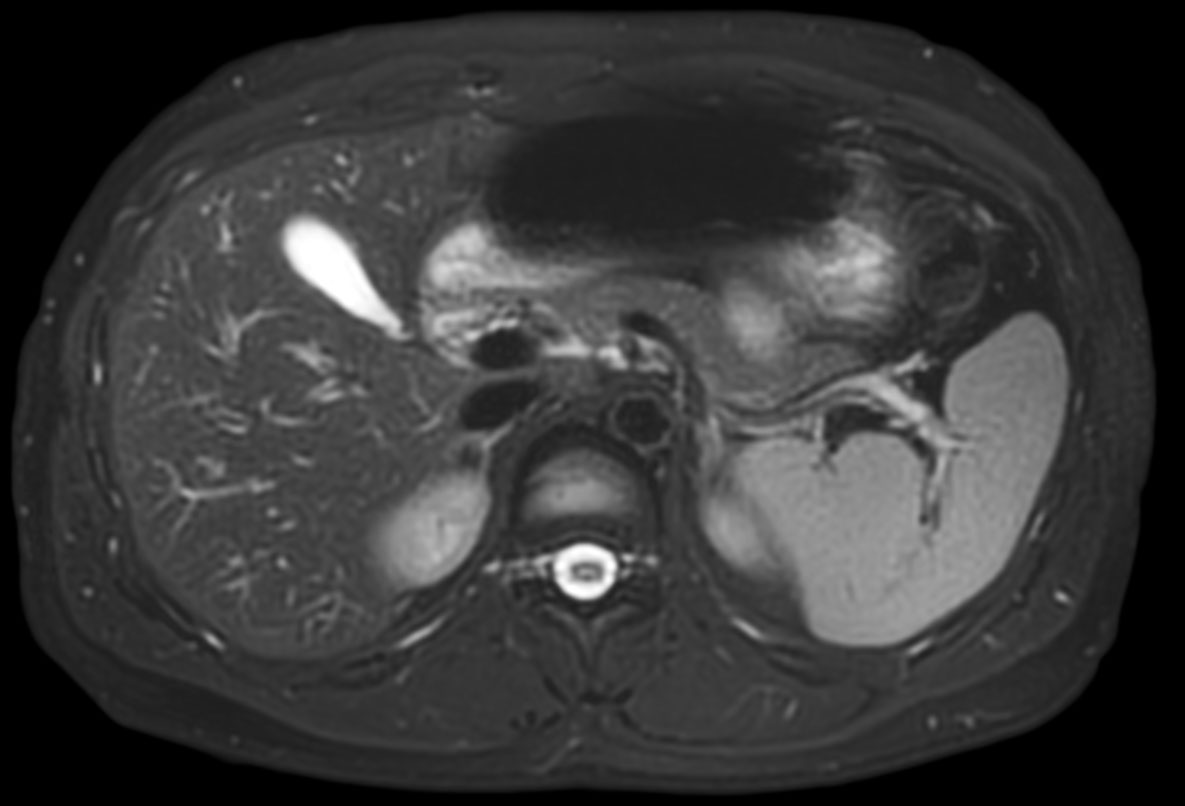

Total torso and liver

• Clinical Application